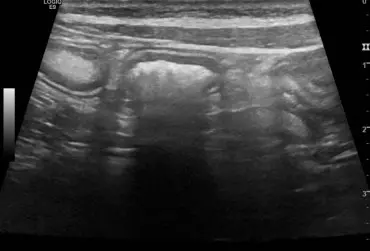

Rzekomołożyskowy przerost błony śluzowej macicy u suk w badaniu ultrasonograficznym

Rzekomołożyskowy przerost błony śluzowej macicy jest rzadko występującą formą przerostu endometrium występującą u młodych suk. Opisano przypadek występowania tej formy przerostu u 18-miesięcznej suki rasy flat coated retriever z wieloma nieswoistymi objawami, w tym przedłużającą się cieczką. W badaniu USG wykryto obecność pięciu zmian miejscowych w rogach macicy w postaci hipoechogennej, pogrubiałej błony śluzowej z obecnością ognisk i pasm hiperechogennych prostopadłych do osi długiej macicy oraz nietypową, hiperechogenną warstwę w centrum. Obraz zmian odpowiadał rzekomo łożyskowemu przerostowi endometrium, natomiast obecność hiperechogennej, wewnętrznej warstwy błony śluzowej macicy mogła wynikać z długości czasu trwania estrus. Zastosowano leczenie zachowawcze aglepriston podawanym podskórnie. Zmiany istotnie zmniejszyły się po zakończeniu leczenia, po czterech miesiącach nie były widoczne.